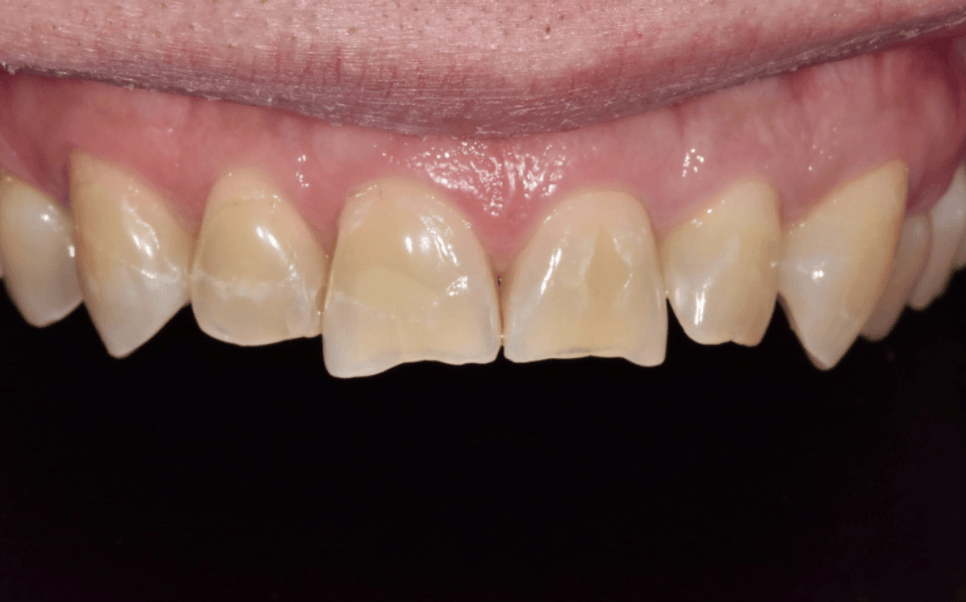

이 환자분은 앞니로 꽃게를 드시다가

앞니 끝(절단은)이 깨져 내원하셨습니다.

사진과 검사상 다행히도

신경이나 뿌리까지 금이 이어진 흔적은

보이지 않았습니다.